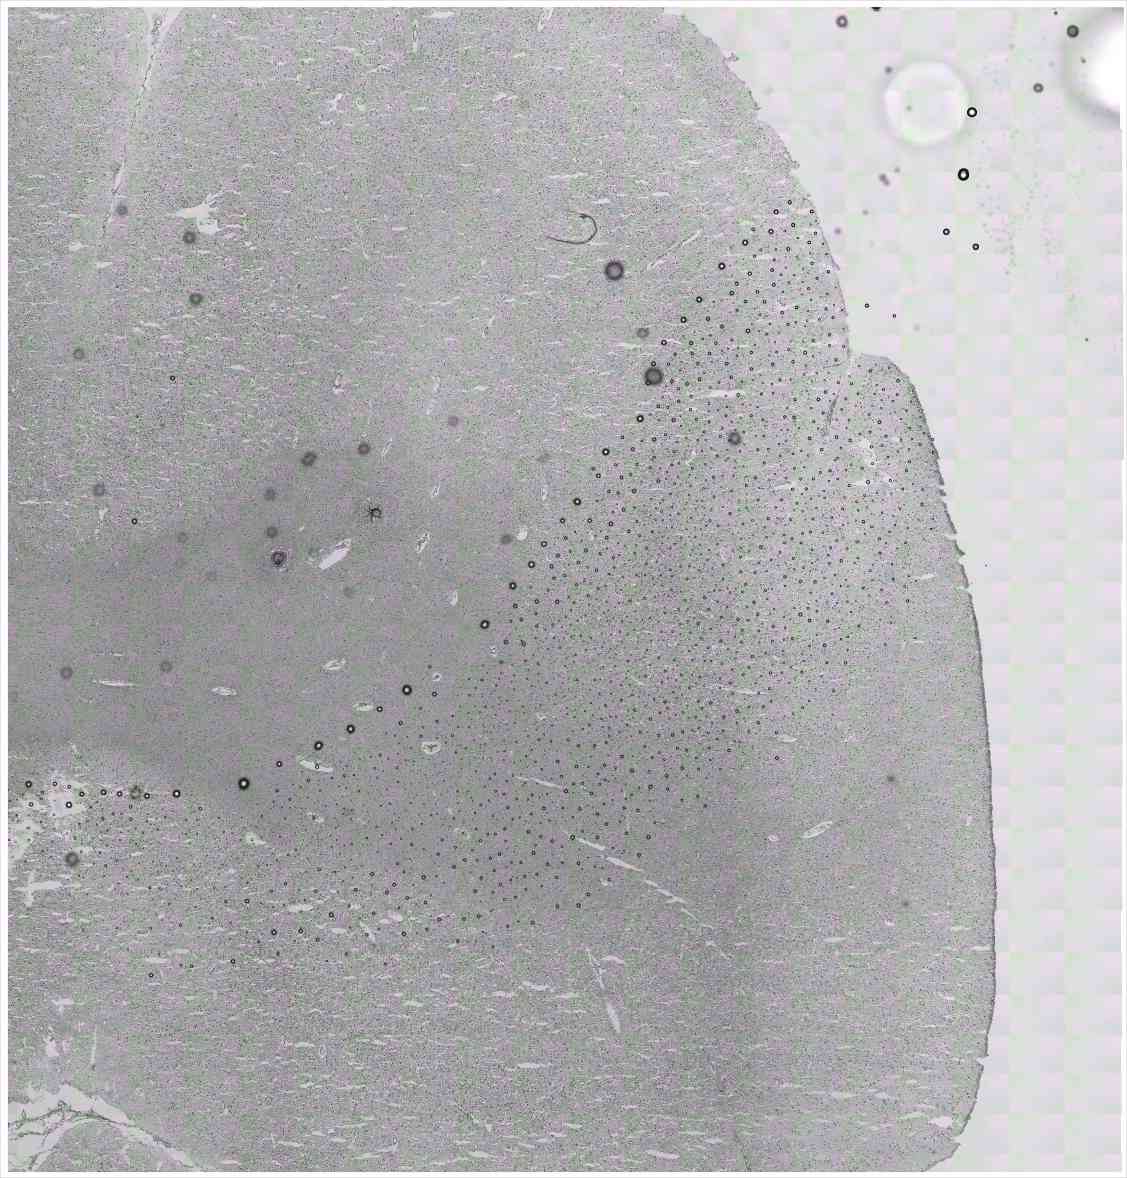

Chip 020 Well D2